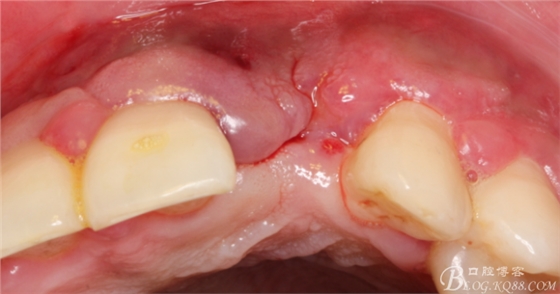

10天拆線一切正常,又過了兩周患者復(fù)診,自述期間無異常。口內(nèi)檢查,真的嚇了一跳,唇側(cè)鼓了個(gè)包,擠壓有白色分泌物溢出,絕對(duì)不是膿液,液體排除后,術(shù)區(qū)觸診空虛,外觀塌陷。這時(shí)候考研大夫的時(shí)刻到了,是先觀察一段時(shí)間再說?還是馬上進(jìn)行處理?我的回答是:馬上處理!如果你沒有及時(shí)處理,而是放患者回家觀察,那么接下來會(huì)發(fā)生如下情況:1.回家后患者家屬及親友會(huì)有很多你可以想象得到的討論;2.患者及家屬會(huì)對(duì)你產(chǎn)生不信任,勢(shì)必會(huì)到其他門診或醫(yī)院檢查,他院大夫會(huì)不會(huì)發(fā)表對(duì)你不利的言論;3甚至?xí)蚁嚓P(guān)法律界人士找你討要說法。

于是我果斷告知患者,手術(shù)失敗了,不能拖延,如不及時(shí)處理,炎癥繼續(xù)發(fā)展會(huì)很快波及鄰牙牙槽骨。患者接受我的建議。切開翻瓣,骨粉及生物膜消失了,骨吸收嚴(yán)重,幸運(yùn)的是,因?yàn)樘幚砑皶r(shí),鄰牙骨支持依然存在。